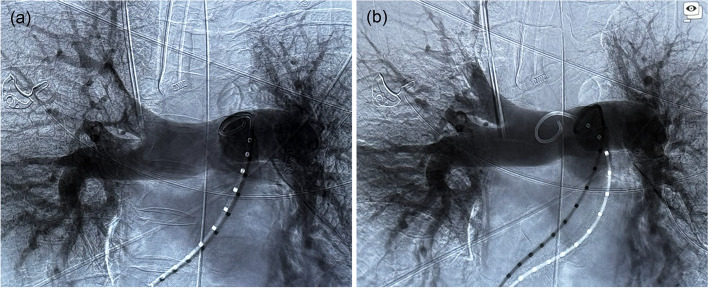

Case presentation: We present a case report of a 73-year-old woman with macroscopic fat pulmonary embolism after a neck of femur fracture. Initially, she had severe circulatory shock, requiring multiple vasopressors and admission to the Intensive Care Unit. A percutaneous large-bore mechanical thrombectomy was performed, after which notable improvements to haemodynamic function and overall clinical trajectory were observed.